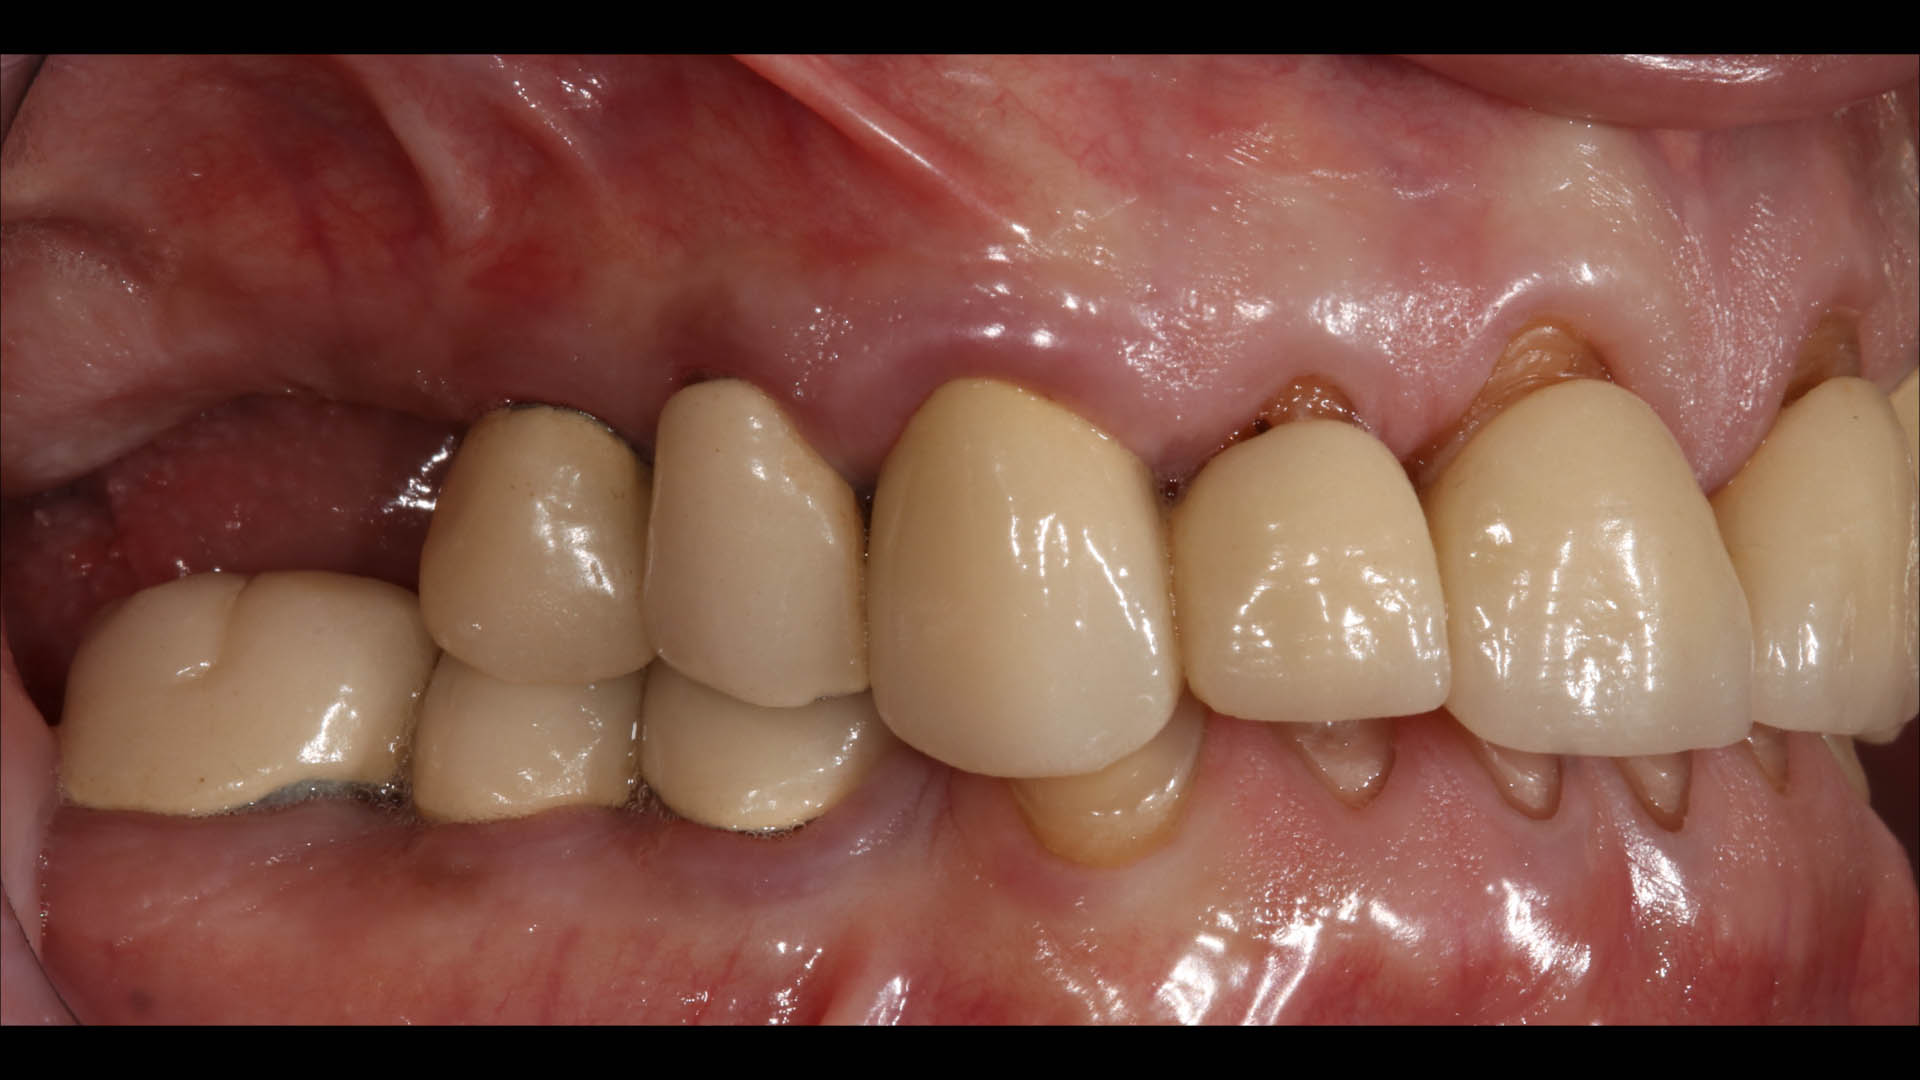

Take a glimpse into the magic of Coral Gables Dentistry through our before and after pictures. See firsthand the incredible smile makeover transformations that have brought confidence and joy to our patients.